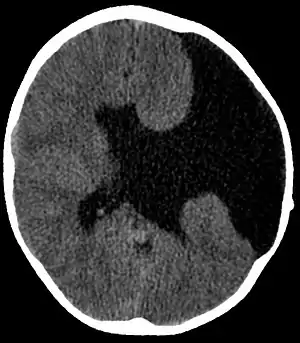

| Axial CT scan showing schizencephaly in a 6-year-old child | |

- Radiological methods like computed tomography (CT) and/or magnetic resonance imaging (MRI) - unilateral or bilateral clefting of the brain.